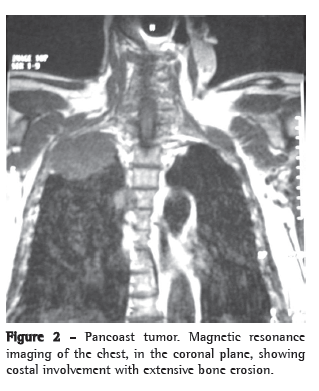

The patient underwent right upper lobectomy with mediastinal lymphadenectomy. Histopathology showed a moderately differentiated adenocarcinoma that was pathologically staged as T1 N2 Mx (Figure 2).